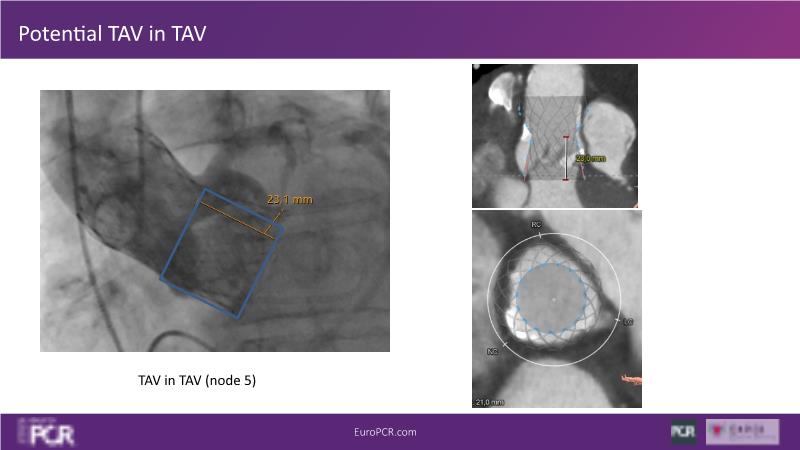

Watch this session to discover insights into patient-prosthesis mismatch and strategies to mitigate risks, delve into the significance of aortic valve commissure for coronary alignment optimization during TAVI, and explore solutions for common TAVI challenges such as peripheral vessel tortuosity and asymmetric valve calcifications in large or small aortic annuli.

- To discuss options to overcome common daily challenges of TAVI: peripheral vessel tortuosity, horizontal aorta, asymmetric valve calcifications in large, or in small aortic annuli